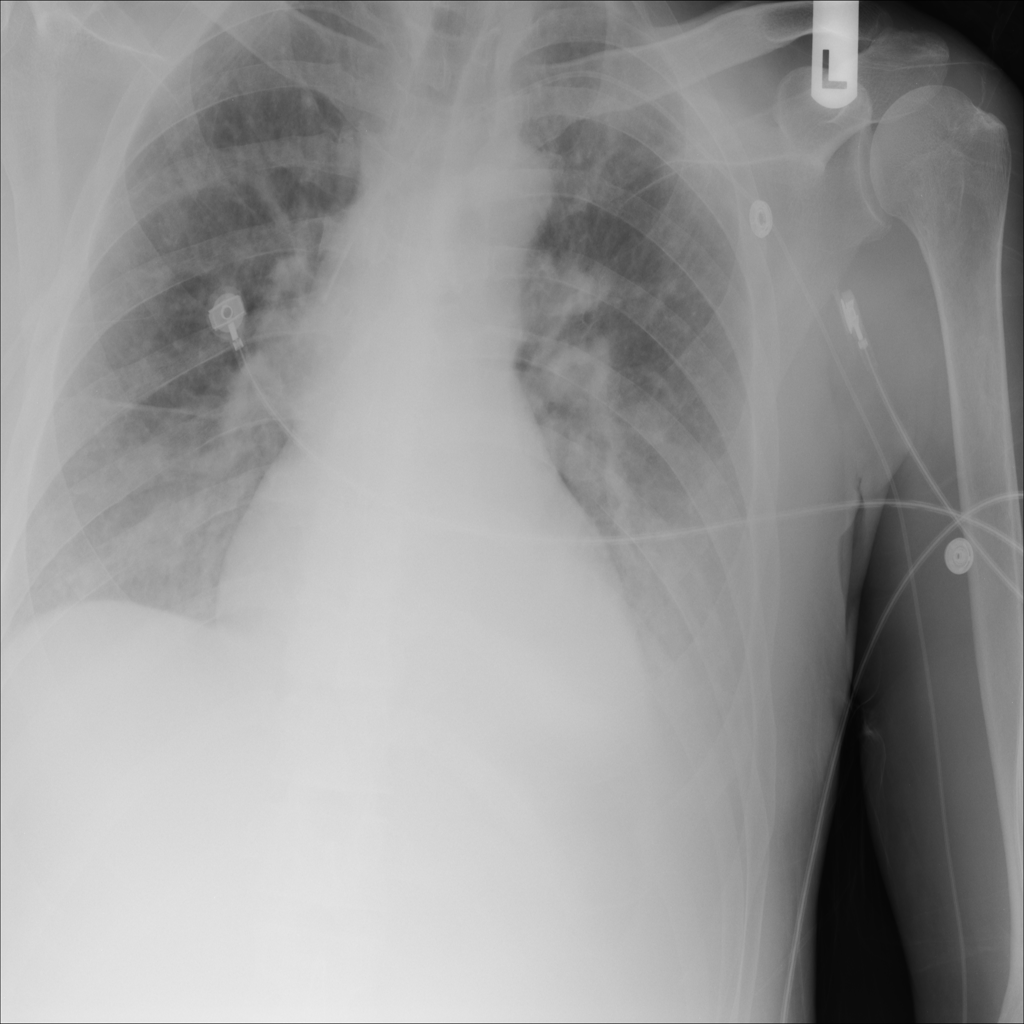

PAT-E828 · IMG-005Edema

PAT-E828 · IMG-005

AP